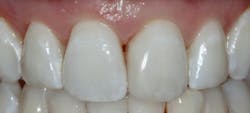

Results

I have found that most posterior teeth can be restored using a single shade. In cases where the tooth structure is very discolored, coupled with a shallow tooth preparation, I opt for an opaque layer beneath my core shade. For anterior cases, the enamel shades offer enough translucency to give the restoration a lifelike appearance. I tend to opt for a core shade to restore chipped incisal edges, and the results have been terrific. Nothing’s worse than a patient coming back with an anterior composite restoration that didn’t hold up; it leads to patients losing confidence in your skills, sometimes negative reviews, wasted chair time, and lost profitability. Polishing this composite is very efficient and effective, and so far, it’s maintained its shine. From my assistants’ perspectives, simplifying my systems made it easier to learn, maintain inventory, and prepare for direct restorations. From my perspective, simplifying composite restorations allows me to reduce chair time, minimize waste, and predictably and efficiently place restorations that my patients love.

G-ænial A’CHORD is a simplified-shade universal composite system that covers the 16 shades in the Classic VITA shade guide in five core shades. It’s indicated for all classes of composite restorations, including diastema closures and composite veneers. In instances where the restoration requires characterization due to translucency or for areas that require more opacity, enamel and opaque shades are available. This material attributes its excellent strength, wear resistance, gloss retention, stain resistance, and radiopacity to GC’s proprietary technologies: full-coverage silane coating (FCS) and high-performance pulverized CERASMART (HPC) fillers.